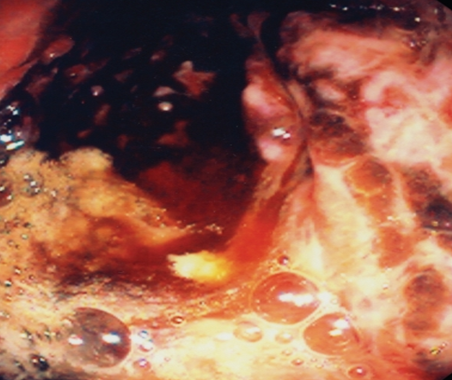

Endoscopic view of multiple gastric stromal tumors after suctioning of hemorrhagic products (Courtesy Dr. V. Penopoulos)